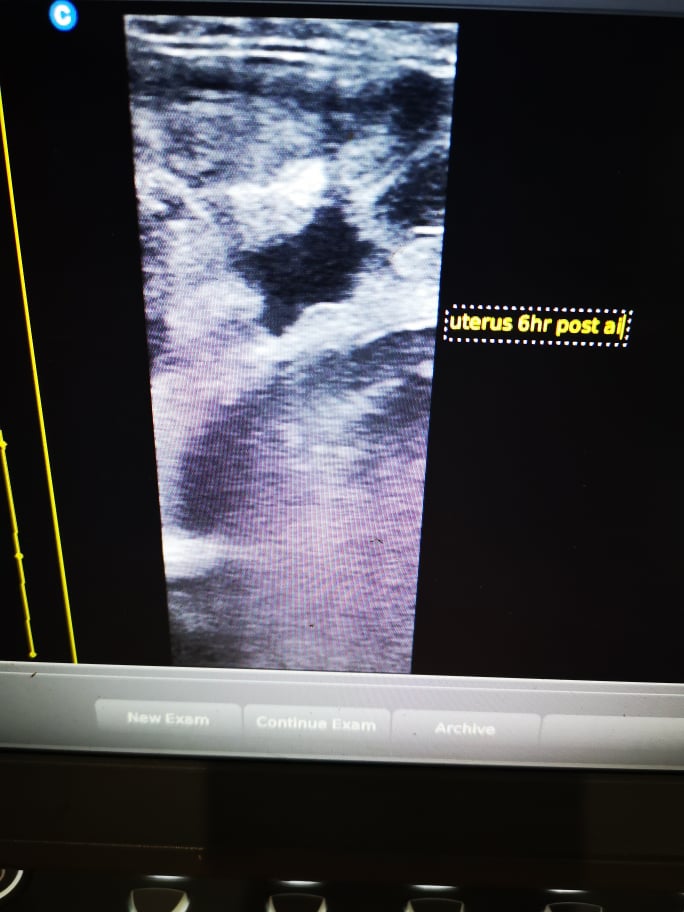

I scanned Sierra again 6 hours later to find minimal fluid, but unfortunately her follicle was still present and hadn't ovulated yet. I had to make a decision and judging a horse show the following day threw a wrench in things, so I decided to get up at 4 AM and check her again. The natural inflammation response of the uterus peaks around 12 hours post AI, but when I checked her I saw she hadn't ovulated yet but was very close and I made the decision to do another partial insemination. I repeated the prepping process above, and sleepily went in again. The semen itself looked pretty good still but I wouldn't call it great so I figured in this case, given that I had to leave for several hours and her uterus was clear from the insemination 12 hours earlier, another small deposit was reasonable. I deposited another 30cc, and caught another hours sleep before I had to leave for the show.

Finally, the last step is to ultrasound again to confirm the semen was properly deposited into the uterus, and track the amount of fluid in the uterus over the hours (or days) that follow. The cervix itself only stays open for about 3.5 days after ovulation, so the window of freeing the uterus of fluid is fairly wide, but still needs to be closely monitored. Often the use of Oxytocin does the trick, but sometimes mares need veterinary attention that requires their uterus being filled with sterile fluid and/or medications, then drained and I try avoid that at all costs.